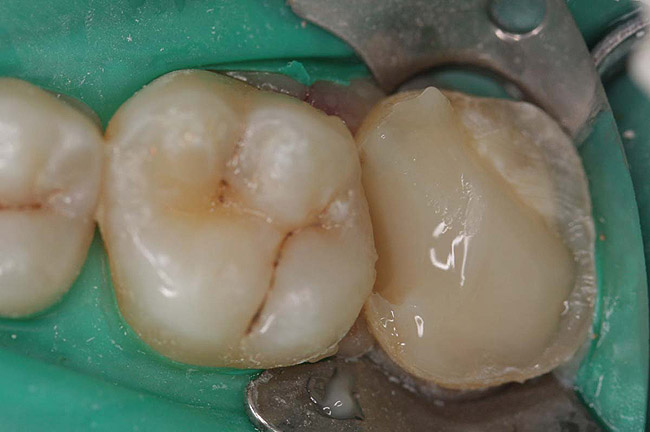

Figure 6  Endodontically treated maxillary right second molar.

Figure 6

Figure 7  Second molar with the palatal canal prepared for post placement.

Figure 7

Case 1

A Class IN maxillary bicuspid was previously restored with a fiber post and an all-porcelain crown (Figure 1). The forces of the oral environment resulted in fracture of the fiber post and crown failure. The remaining fiber post in the root was removed, and anti-rotational areas were prepared for a cast post (Figure 2). A gold cast post was constructed at a dental laboratory, using an indirect technique (Figure 3). A porcelain-fused-to-metal (PFM) crown was constructed with a bevel finish to provide a ferrule and reduce forces on the post (Figure 4 and Figure 5).